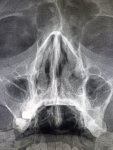

Где пиздецома?

Аноним 09/12/25 Втр 08:27:51 #47 №327475609

>>327476174

Левую гайморову залепило.

Гайморит слева (пристеночное утолщение слизистой) и вставные зубы